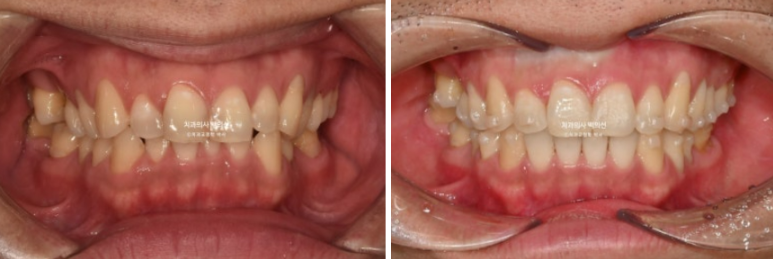

24.05~25.03

중심선 불일치와 심한 과개교합, 송곳니 덧니 등이 보입니다.

24.05~24.11

과개교합은 완벽히 개선이 되었고